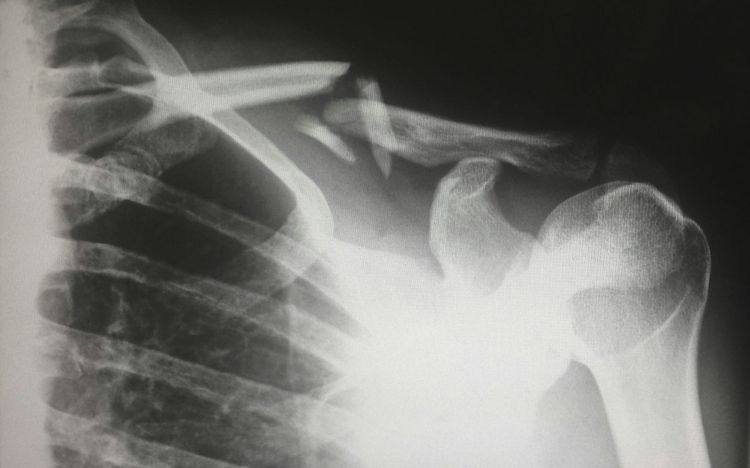

Section B: Rehab after fracture

Initiation and progression of resistance Flowers et al. (2022) review is currently the only study combining clinical and physiotherapy setting.